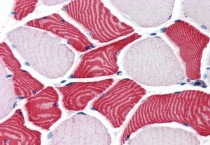

ARG63995 anti-EBAG9 / RCAS1 antibody IHC-P image

Immunohistochemistry: Paraffin-embedded Human skeletal muscle tissue. Antigen Retrieval: Steam tissue section in Citrate buffer (pH 6.0). The tissue section was stained with ARG63995 anti-EBAG9 / RCAS1 antibody at 3.75 µg/ml dilution followed by AP-staining.